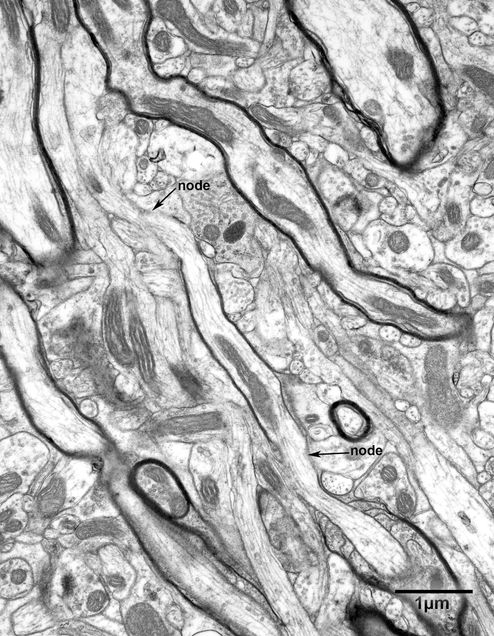

Figure 8.4

A bundle of nerve fibers in layer 4 of the primary visual cortex of a 25 year old monkey. One of the nerve fibers is surrounded by a sheath of myelin that is only one lamella thick. The sheath is only three microns long. At each end of the sheath the nodes of Ranvier (nodes) are visible. The thickness of the sheath and the short length of the internode suggest that remyelination is occurring.